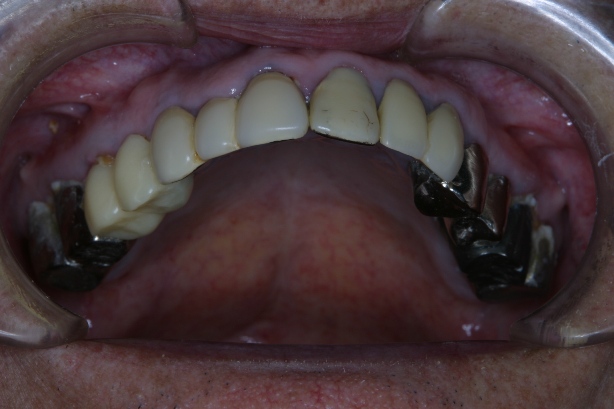

「8020運動」 表彰に出て頂いた方々のお口を拝見